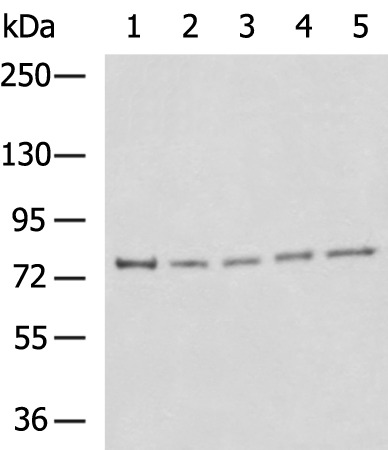

分类: 科研抗体货号: P07512别名: MEK3; MKK3; MAPKK3; PRKMK3; SAPKK2; SAPKK-2应用: WB,IHC反应种属: Human, Mouse